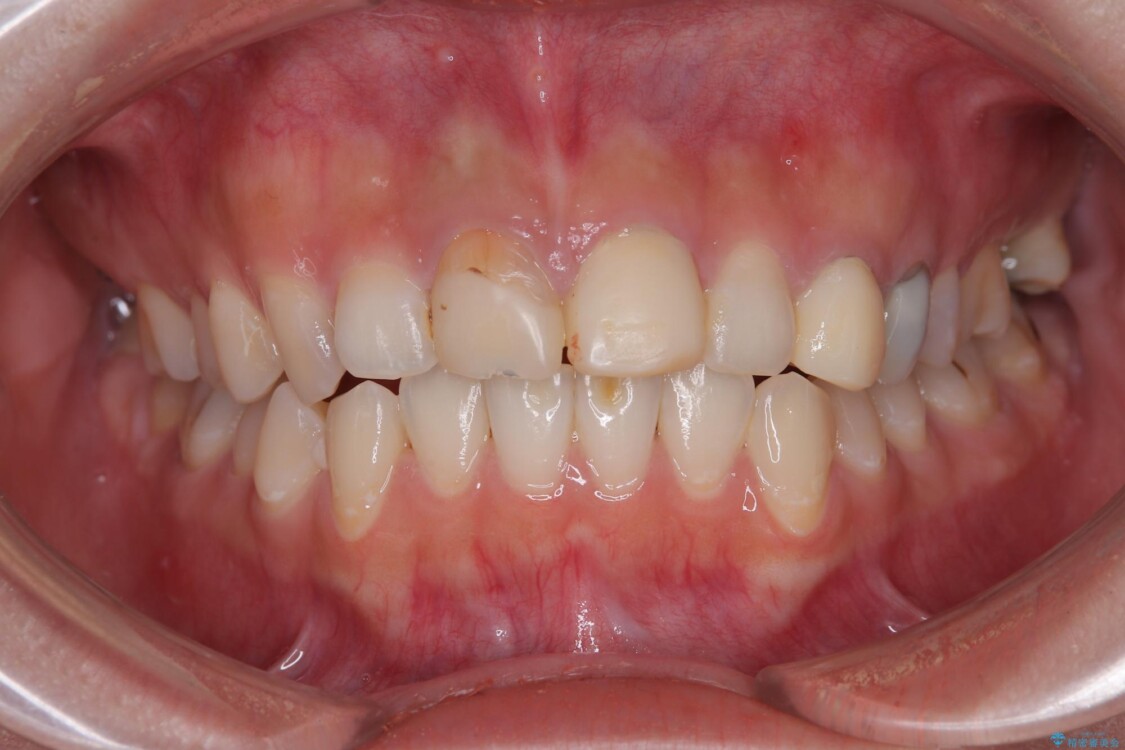

治療後

• 「抜歯してブリッジ」と言われた20代女性が選んだ治療とは|たった4か月で自然な笑顔に抜歯即時インプラント+審美補綴の症例 治療後画像